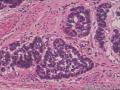

胃癌,类型?

性别

男

年龄

69

临床诊断

胃癌

一般病史

标本名称

大体所见

溃疡性肿块

参考诊断

低分化腺癌,神经内分泌癌?

低分化腺癌倾向神经内分泌癌